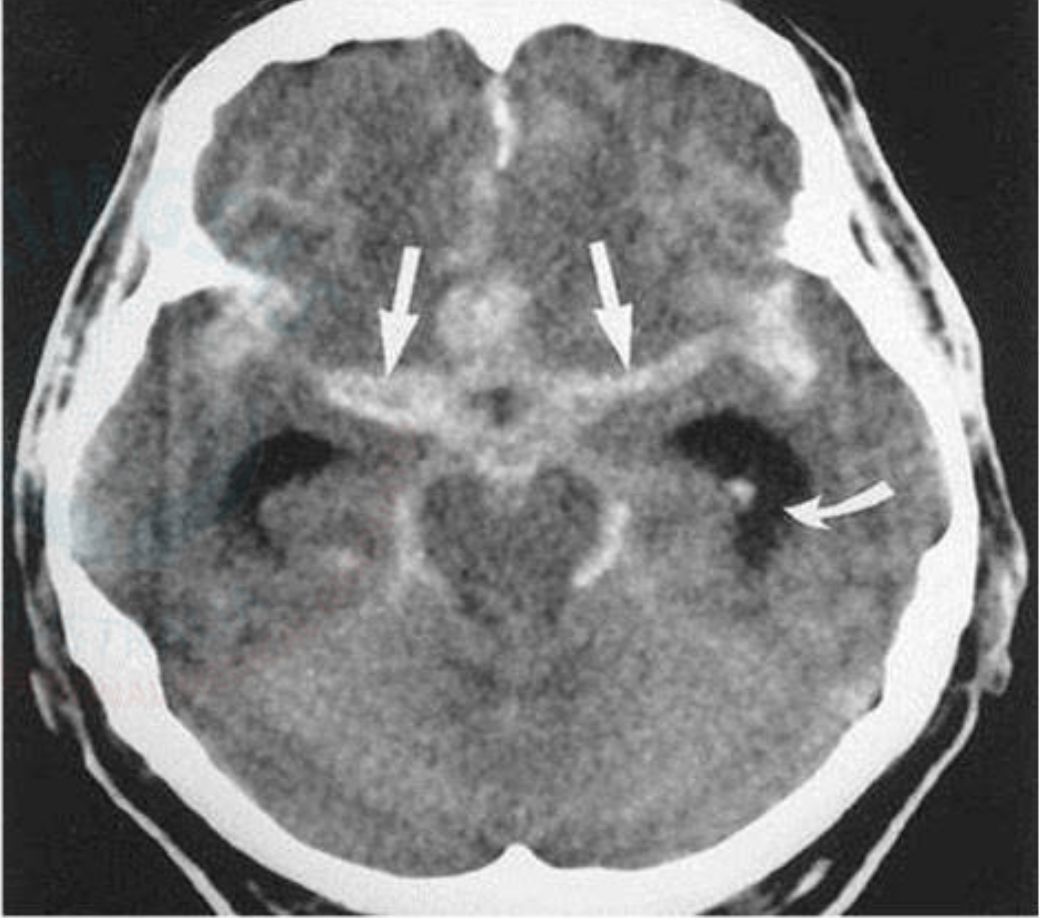

Headache: Subarachnoid Hemorrhage CT Imagen

Areas of hyper density within the cisterns and sulci